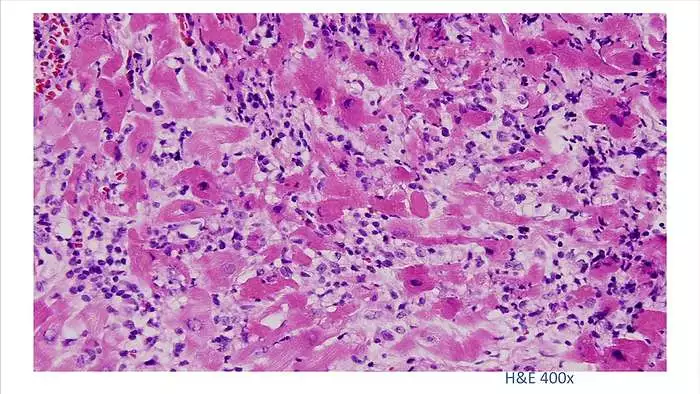

7.

100倍还不是看得很清楚,放大400倍就很明显了,一个个蓝点就是淋巴球。这是很厉害的猛暴性心肌炎,整个心脏都被淋巴球浸润了。